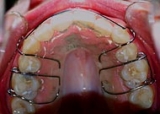

![]() |

| Unauffällig geklebte Drähte auf der Innenseite | Abnehmbare Geräte, Platten, häufig nur nachts getragen | Positioner. |